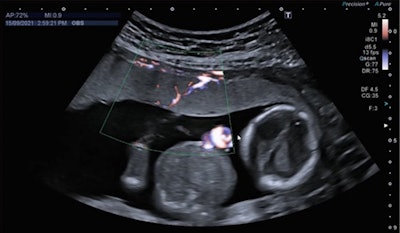

The researchers used Doppler ultrasound for the new, experimental treatment method. Here, high-intensity focused ultrasound energy heats blood vessels precisely and blocks blood flow. This allows the blood flow between the twins to become rebalanced.